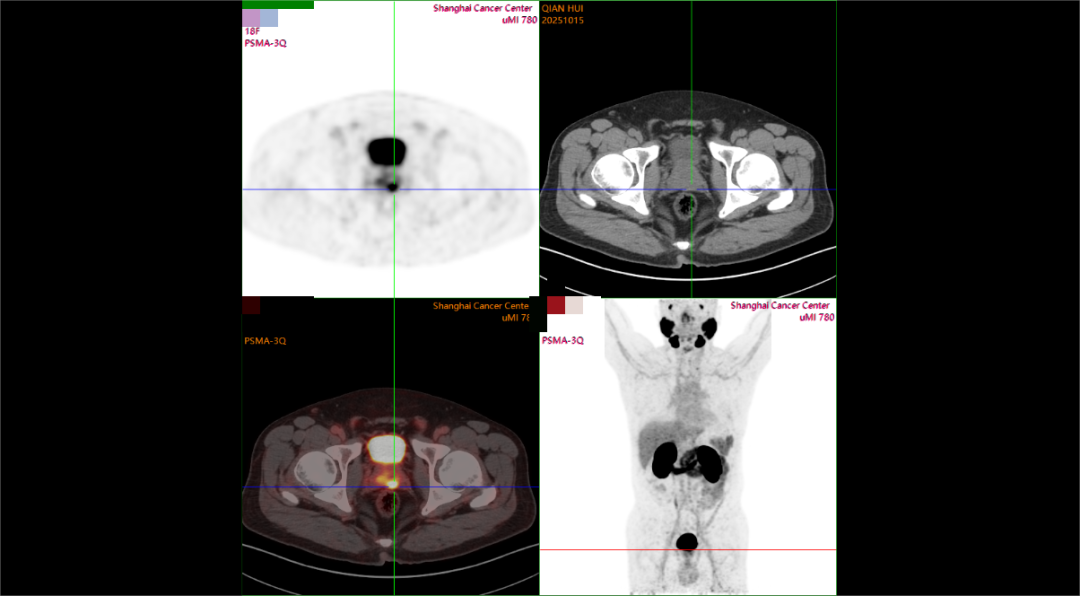

现病史:患者PSA 两年来持续升高,2025年10月PSA:8.68,外院MRI:pi-rads 2分。2025年10月10日我院穿刺,前列腺腺泡腺癌,Gleason评分:3+3=6,现为进一步诊疗入院。病理报告(2025.10.10):前列腺腺泡腺癌,GIeason评分:3+3=6 ;lSUP分组:1累及组织约20%;核医学报告(2025.10.16):前列腺形态欠规则,体积正常,最大横截面约4.6*3.6cm,左侧外周带PSMA摄取增高灶。